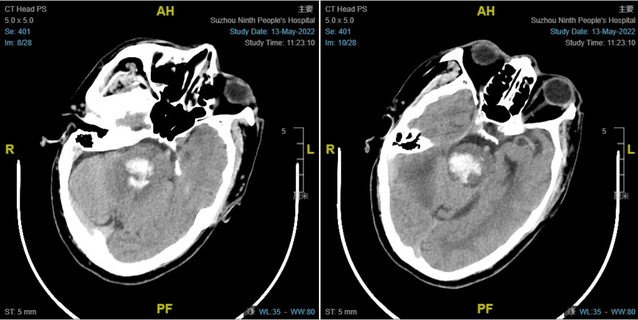

5月13日,患者蒋某某因突发昏迷由120急送至九院急诊抢救,急诊科医生接诊后迅速判断病情:患者昏迷,左侧肢体肌张力高,考虑脑出血可能。急查CT明确:脑干出血。患者脑干出血量大,严重危及生命。神经外科医师接到急会诊通知后迅速到场,并将患者收入神经重症监护病房行进一步诊治。

历经5个小时,手术取得了成功,术后复查CT示脑干血肿清除完全,减压充分。术后,神经重症医护团队为患者制定了详尽的治疗及护理方案。在医护的共同努力下,患者术后第二天意识即逐渐开始好转,术后第三天,可言语,肢体可活动。经过10余天的治疗,患者病情进一步好转出院。接下去,将进行下一步综合康复治疗。